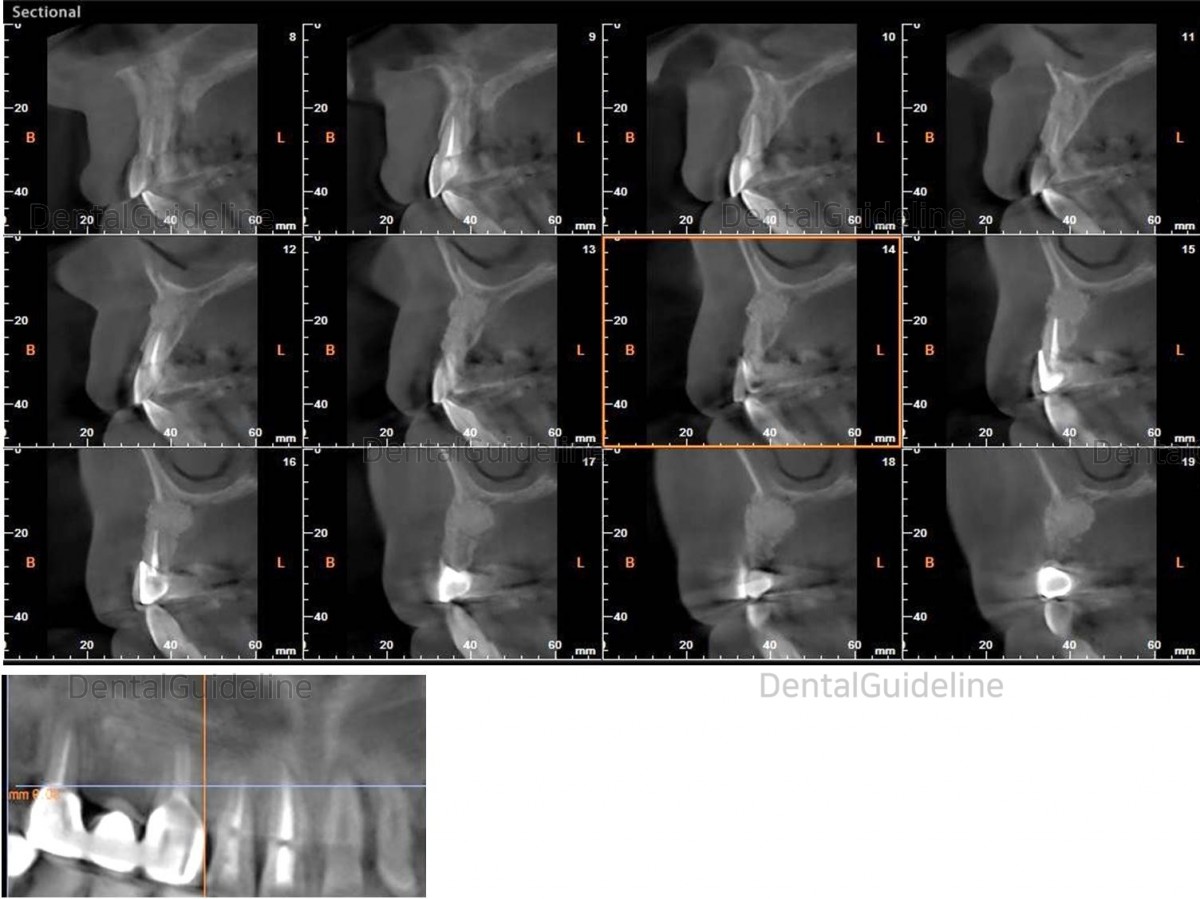

3. CBCT

16. CBCT 5 months after the surgery.